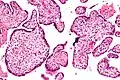

| Micrograph of villitis of unknown etiology. H&E stain. | |

Villitis of unknown etiology (VUE), also known as chronic villitis, is a placental injury. VUE is an inflammatory condition involving the chorionic villi (placental villi). VUE is a recurrent condition and can be associated with intrauterine growth restriction (IUGR). IUGR involves the poor growth of the foetus, stillbirth, miscarriage, and premature delivery.[1][2] VUE recurs in about 1/3 of subsequent pregnancies.[3]

VUE is a common lesion characterised by inflammation in the placental chorionic villi. VUE is also characterised by the transfer of maternal lymphocytes across the placenta.[2]

Histomorphologically, VUE is characterized by a lymphocytic infiltrate of the chorionic villi without a demonstrable cause. Plasma cells should be absent; the presence of plasma cells suggests an infective etiology, e.g. CMV infection.